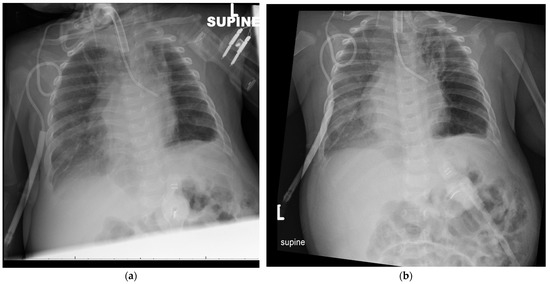

2. Case Presentation